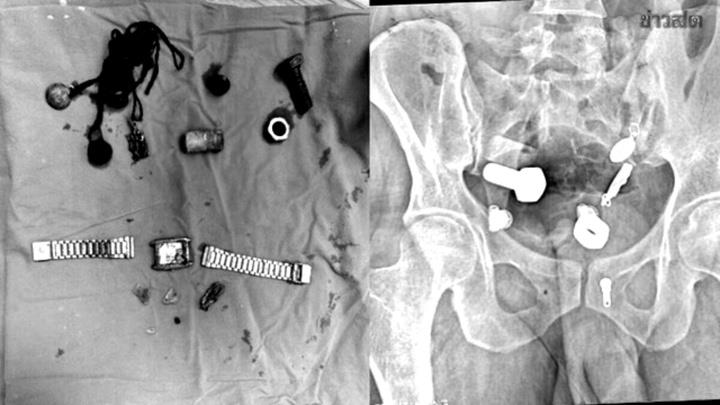

Do đau bụng dữ dội không thể ăn uống, người đàn ông được đưa đi cấp cứu. Các bác sĩ đã kinh ngạc khi phát hiện một chiếc đồng hồ và ốc vít nằm trong bụng anh ta.